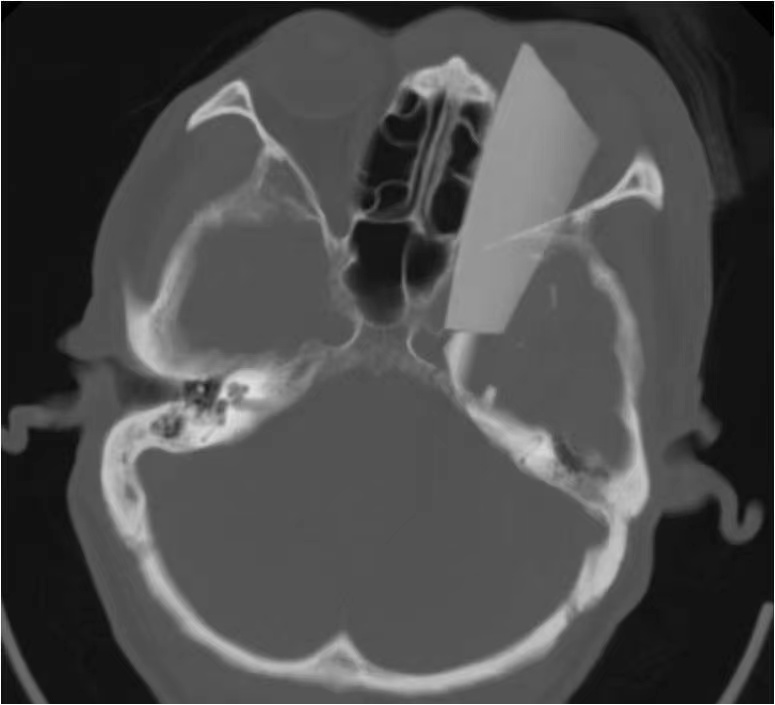

在充分术前准备和各科室的紧密配合下,一场“虎口拔牙”式的开颅探查+异物取出手术在中心手术室1号杂交手术间紧张有序地开始了。神经外科康军主任坐镇指挥,手术室王蕊、李家兴护士迅速完成各项准备,麻醉科吴黎黎医生为病人进行全身麻醉。神经外科王卫医生首先为患者进行全脑血管造影术(DSA),造影结果显示异物与颅内海绵窦段颈内动脉“擦身而过”,最近处仅有不足2毫米的间隙!玻璃断茬异常锐利,在拔出过程中稍有不慎,就很有可能伤及颅内大血管,引起致命大出血。王卫医生又给患者做了压颈试验,证实前交通动脉代偿良好。如果现在闭塞左侧颈内动脉,手术风险和医生压力将会大大降低,但患者会面临迟发偏瘫或将来脑供血不足等风险,神经外科医生们又面临一个两难选择。经过现场认真讨论,为保证患者术后能拥有高质量的健康生活,康军主任果断决定:力争为患者保留颈内动脉畅通,同时留置腹股沟处介入血管穿刺鞘,万一术中出现大出血情况可以迅速闭塞患侧颈内动脉近端。

患者造影结果